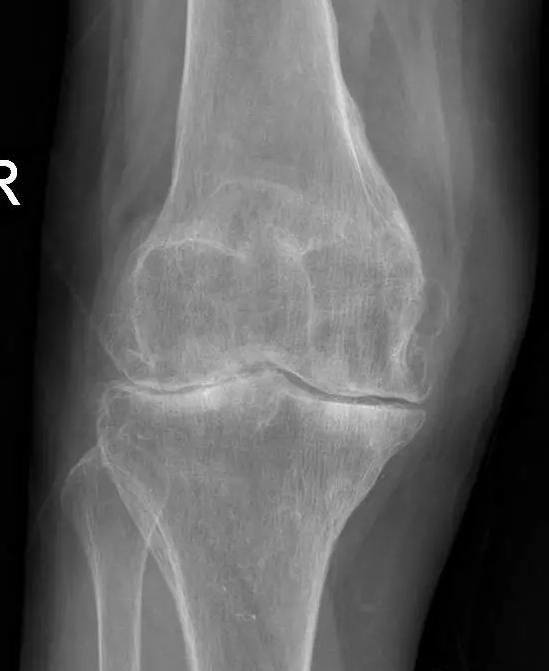

晚期:骨关节炎表现为膝关节明显疼痛,休息后常无缓解,伴有活动受限,可并发畸形,X 线片可见关节周围有明显的骨赘形成,或可见游离体,关节间隙明显狭窄,甚至消失。

术前片: